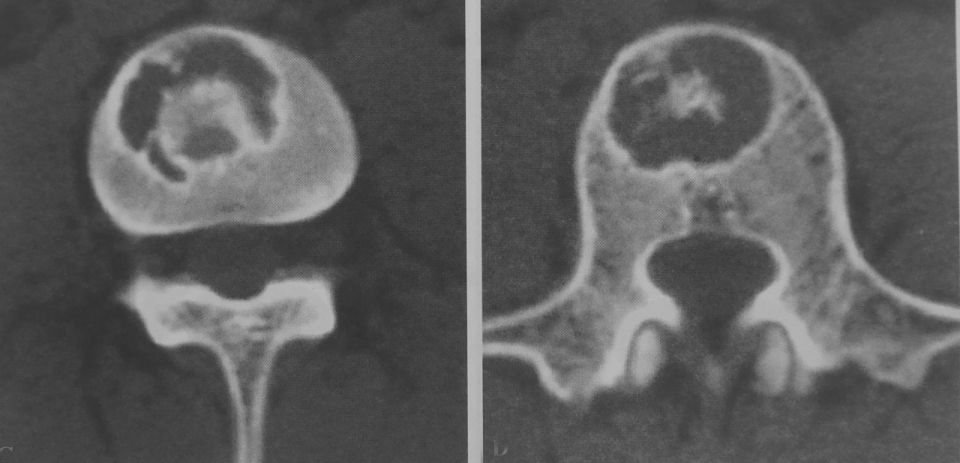

图 5.膨胀性破坏:动脉瘤样骨囊肿

图 6.膨胀性破坏:骨巨细胞瘤